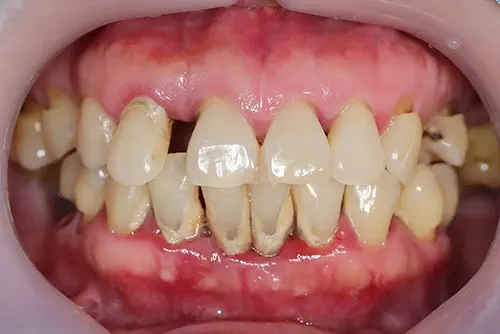

Do you have these signs and symptoms of periodontal disease?

- Bleeding gums – Gums should not bleed.

- Loose teeth – Caused by bone loss or weakened surrounding structures,

- Spacing between teeth – Caused by bone loss.

- Receding gums – Loss of gum around a tooth.

- Red and puffy gums – Gums should not be red or swollen.

- Tenderness or Discomfort – Gum inflammation from plaque, calculus and bacteria build up.